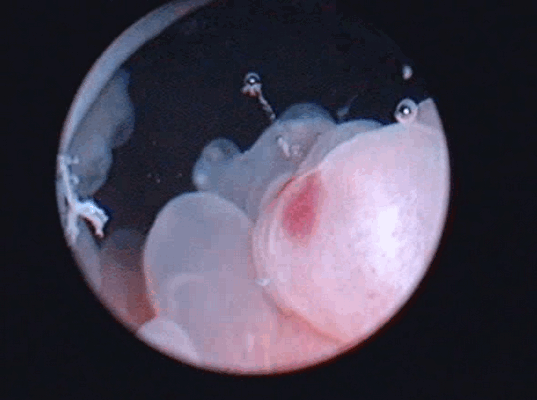

Цистоскопическое обследование пациентки О.

Цистоскопическая картина солидного образования

По данным ультрасонографии ретенционные изменения верхних мочевых путей с обеих сторон были выявлены у пациентки О., 35 лет, (чашечки и лоханка справа 16 и 32 мм, слева – 15 и 35 мм соответственно, у остальных пиелокаликоэктазии не было. Больным была выполнена цистоскопия, по данным которой в 3 случаях определялось стелящееся солидное образование в диаметре около 8 см (пациентка О., 35 лет), 5,6 (пациент М., 43 лет) и 2,8 см (пациент С., 56 лет) с явлениями буллезного отека, распада, кровоизлияний и инкрустацией мочевыми солями Образования предположительно характеризовались инфильтративным характером роста.